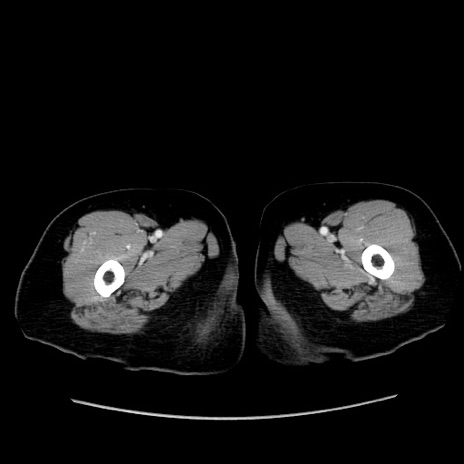

症例19(横断像)

【症例】80歳代女性

【主訴】下腹部痛

【現病歴】約8時間前より下腹部痛の出現あり、救急外来受診。

【既往歴】両側付属器切除

【身体所見】意識清明、下腹部正中に手術痕あり、その部位に一致して圧痛と反跳痛あり。腸蠕動音は亢進。

【データ】WBC 9300、CRP 0.15